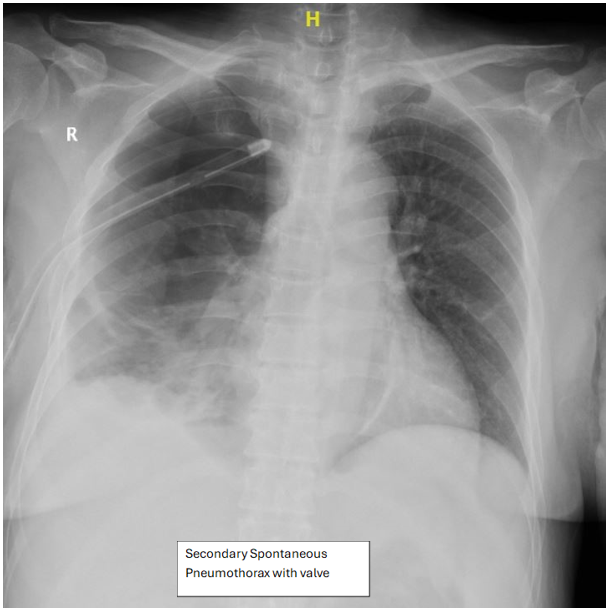

• The Heimlich valve group was used primarily for younger patients with primary or recurrent spontaneous pneumothorax, often reluctant to undergo surgery.

Figure 4